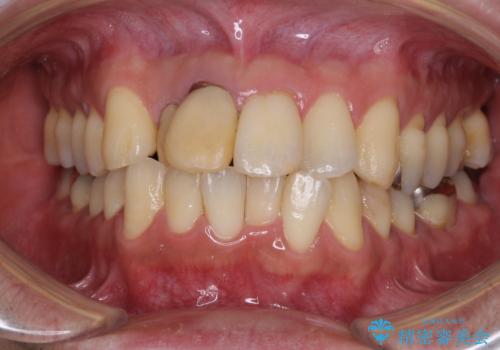

セラミック治療 → 前歯クラウン(オールセラミック)

前歯の見た目を良くしたい オールセラミッククラウン

前歯を綺麗にしたい オールセラミッククラウン

前歯のがたつき 保険治療の前歯の被せ物もやりかえたい